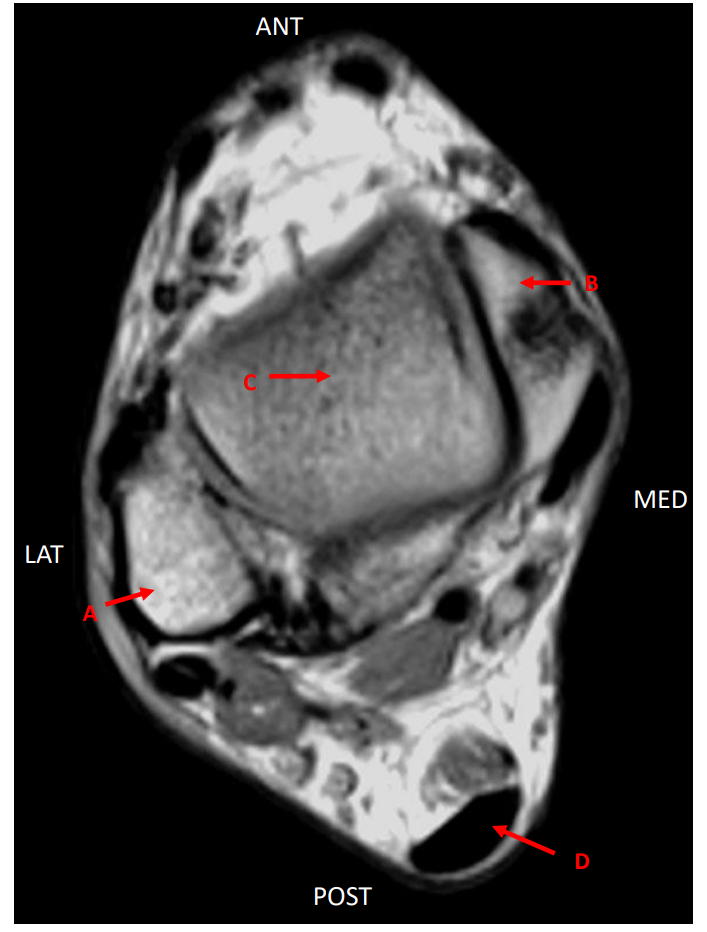

Hvilken vekting?

T1

Hvilket plan?

Transversalplan

A

Malleolus lateralis

B

Malleolus medialis

C

Os talus

D

Tendo calcaneus (achilles)